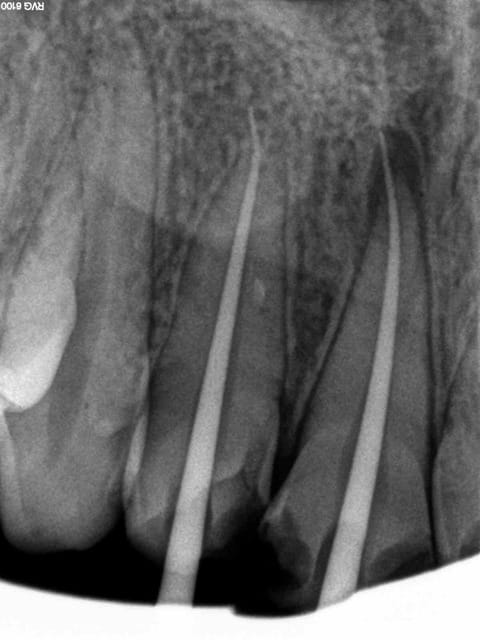

Et 1 h plus tard, fin du massacre conventionnel, no post no crown !.-)))

3 cvcjke - Eugenol

1 guqoin - Eugenol

2 v4h37g - Eugenol

4 s7ibd3 - Eugenol

5 ikfkap - Eugenol